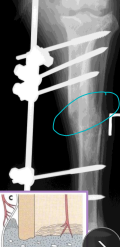

Normal Blood Supply of Long Bones

Proper Nutrient artery: medullary cavity (30%), inner 2/3 cortical bone (70%)

Medullary circulation is mostly disrupted → fracture

Metaphyseal arteries: proximal & distal metaphyseal

Hypertrophy if nutrient artery is damaged

Periosteal arteries: outer 1/3 cortical bone

Primary circulation in fractures

Epiphyseal arteries: supply epiphysis only (do not cross physis)

Nonunion: No progression on rads for 3+ months, instability, poor blood supply

Vascular (viable): callus present, fracture line persists

Tx: stabilize, remove implants, align

Avascular (non-viable): little/no callus, poor biology

Tx: curettage, rigid fixation, cancellous graft, remove loose implants